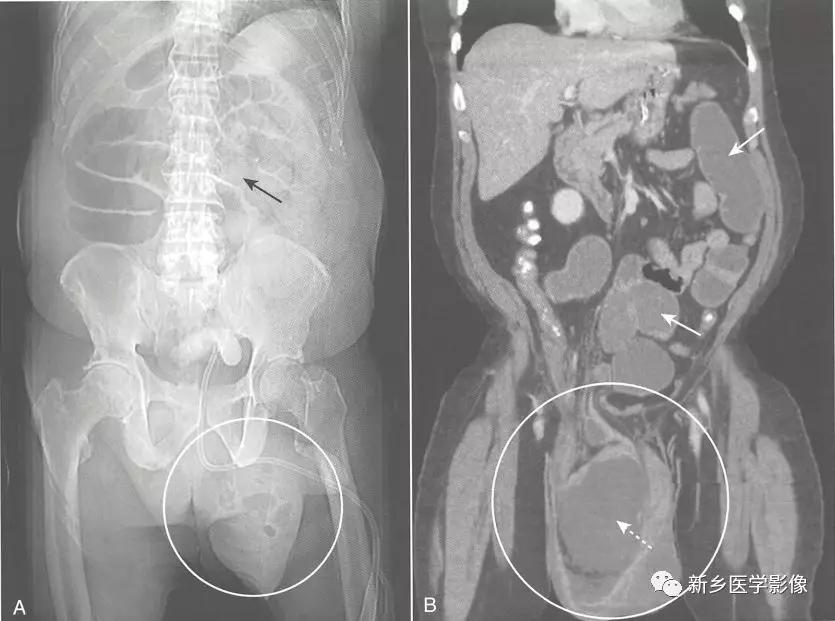

1、病理生理学: 存在一种结肠内部或外部的病变阻塞肠腔。随着时间推移,结肠将从梗阻点逆行扩张,即使梗阻最远端位于乙,状结肠,盲肠也通常在扩张的结肠中直径最大。

大肠正常具有吸收水的功能,所以在梗阻的结肠中很少见到或没有气-液平面。随着时间推移,持续的蠕动波将推动梗阻远端的结肠内容物向前移动至排出。在机械性大肠梗阻中,在直肠中通常很少见到或没有气体影。

梗阻近端结肠扩张。

由于大肠肠襻数目有限,且不互相重叠(如小肠肠襻),所以有时可以通过观察最后含气的结肠肠段来确定梗阻部位。

不论肠梗阻部位在何处,盲肠往往是结肠的扩张最严重的肠段,当盲肠直径达到15cm以上时,须警惕盲肠破裂的风险。

小肠不扩张(除非回盲瓣功能不全)。

因为直肠常常位于梗阻部位以远,所以直肠内包含很少气体或没有气体。

由于大肠具有重新吸收水的功能,大肠内通常没有或很少气-液平面。

只要回盲瓣可以阻止气体逆行进入小肠( 即回盲瓣功能完整),结肠将在回盲瓣和结肠梗阻部位间继续扩张,而小肠不扩张。

-

但如果结肠内压力过高导致回盲瓣开放(即回盲瓣功能不全),气体将从扩张的大肠逆行进入小肠,就像空气从气球逸出一样。

此时,相对于塌陷的大肠,小肠显示出不成比例的扩张,即可类似机械性小肠梗阻。

解决方案: 进行腹部CT扫描,它可以显示梗阻的部位在结肠,而不是小肠。

CT可用来确定梗阻原因、评估是否存在腹腔游离气体以及明确相关并发症,如肝脏或淋巴结转移等。

在梗阻部位近端大肠肠腔扩张,在梗阻部位远端肠腔直径恢复正常。

梗阻处通常是结肠癌造成,在CT上表现为软组织肿块,累及大肠的疝也很容易在CT上显示。